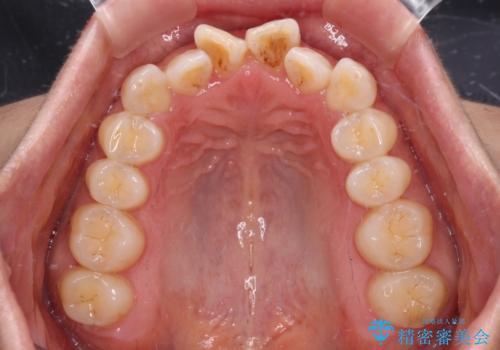

【モニター】飛び出した上顎前歯 補助装置を併用したインビザライン矯正治療

- 上下前歯が非接触となり、前方に突出していることを気にして来院された患者様です。

上下の前後差が大きいため、インビザライン単独での上顎歯列移動は困難と判断し、補助装置により上顎歯列を後方移動させ、その後インビザラインにて仕上げていくこととしました。

また、舌の突出癖が非接触の原因の大きな要因と考えられるため、舌のトレーニングをしっかり行っていくよう指導しました。

補助装置なしでも改善できる可能性はありましたが、補助装置で確実性を上げ、短期間できっちりと仕上げることができました。